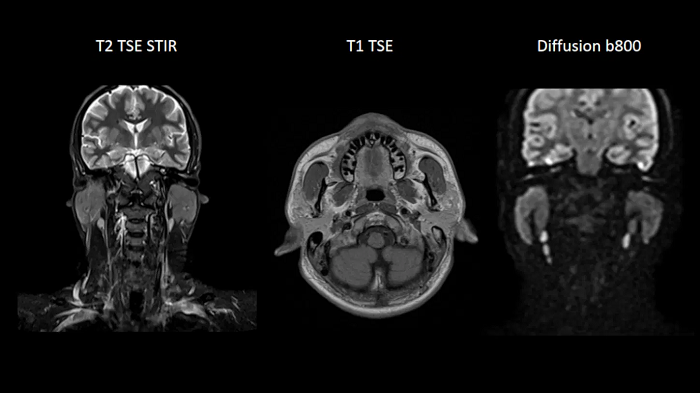

Neck

Excellent soft tissue contrast in the neck

An all-inclusive soft tissue investigation in the head with outstanding image quality for T1, T2, and diffusion contrast.

MAC-ID: 7aaaa0158. Image Credit: Siemens Healthineers